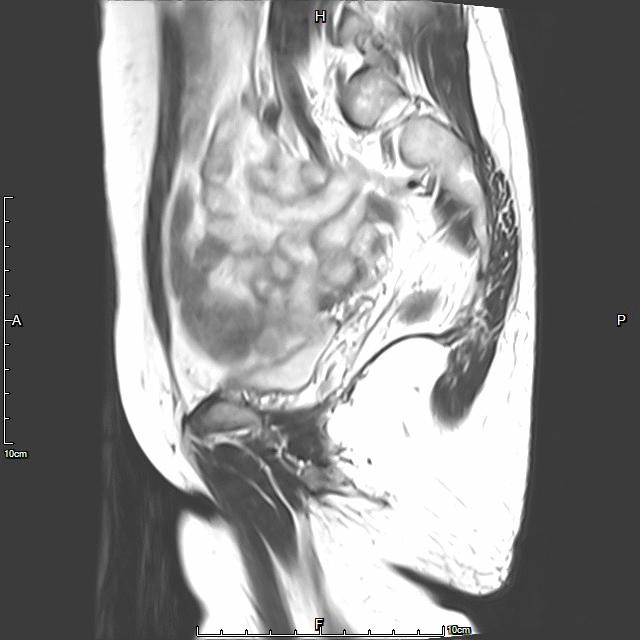

例2

中年患者,患有“子宫腺肌瘤”7年余,长期受痛经、月经量增多困扰,严重影响生活质量。经多处求医,经历药物调理、“曼月乐”宫腔植入、“海扶刀”消融术等多种治疗,痛经、月经量多等情况一直无法有效缓解,日渐严重。

- 术前MRI检查显示子宫明显增大。

术前MRI检查显示子宫明显增大

- 经UAE治疗后,术后痛经、月经量增多等症状迅速得到缓解,生活质量明显改善。术后3月上述症状基本消失。

- 术后4个月复查,子宫明显缩小,腺肌瘤明显坏死吸收,相关症状基本消失。

术后复查MRI显示子宫明显缩小,腺肌瘤明显坏死吸收